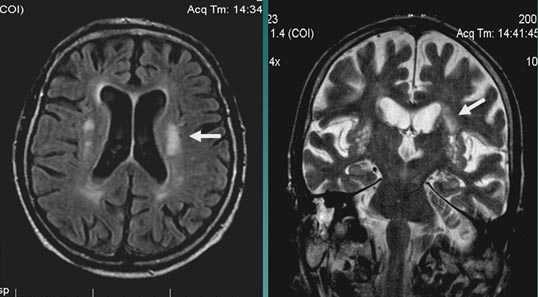

Валлеровская дегенерация вследствие инсульта в бассейне средней мозговой артерии в левом полушарии большого мозга. Р1_А1К-изображения (а, b) и Т2-ВИ в аксиальной плоскости (с). В зоне, кровоснабжаемой левой средней мозговой артерией, визуализируется кистозный дефект с глиозом (а). Определяется повышенная интенсивность сигнала от пирамидного пути в левой ножке мозга (b) и в продолговатом мозге слева (с).

- Стадия 1 (острая): До 4 нед. после повреждения на традиционных МР-изображениях не определяются патологические изменения сигнала.

- Стадия 2 (подострая): Спустя 4-14 нед. на Т2-ВИ визуализируется гипоинтенсивная зона, обусловленная начальным, а не биохимическим распадом миелина и компонентов аксона.

- Стадия 3 (хроническая): Гиперинтенсивная зона на Т2-ВИ (распад жиров и липопротеинов, вазогенный отек, глиоз).

- Стадия 4: Атрофия

- Раннее выявление возможно при использовании метода переноса намагниченности (ПМ) и диффузионно-взвешенных изображений.